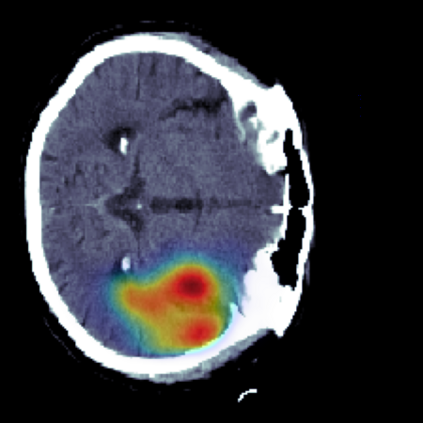

The sigmoid activation is the standard output activation function in binary classification and segmentation with neural networks. Still, there exist a variety of other potential output activation functions, which may lead to improved results in medical image segmentation. In this work, we consider how the asymptotic behavior of different output activation and loss functions affects the prediction probabilities and the corresponding segmentation errors. For cross entropy, we show that a faster rate of change of the activation function correlates with better predictions, while a slower rate of change can improve the calibration of probabilities. For dice loss, we found that the arctangent activation function is superior to the sigmoid function. Furthermore, we provide a test space for arbitrary output activation functions in the area of medical image segmentation. We tested seven activation functions in combination with three loss functions on four different medical image segmentation tasks to provide a classification of which function is best suited in this application scenario.